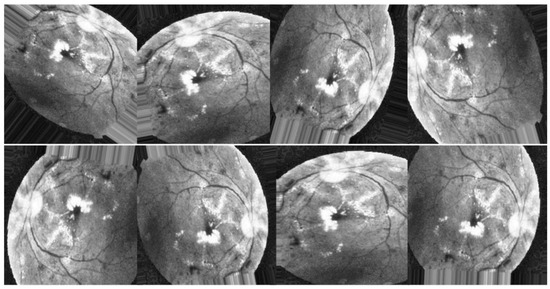

All previous edits to images in the training set are applied to generate new samples for the network. While the total number of images is the same in all scenarios, Figure 8, Figure 9 and Figure 10 illustrate the purpose of data augmentation, which is to increase the quantity of data by providing slightly altered copies of the existing data or newly synthesized data derived from the existing data using the same parameters in all three scenarios. Here are the three scenarios that were used to train DenseNet-121:

Finally, in the third scenario, augmentation techniques are applied to the enhanced images utilizing HIST, CLAHE, and ESRGAN, respectively, as depicted in Figure 10.

Figure 10. Examples of augmenting the same image with different methods (HIST + CLAHE + ESRGAN).